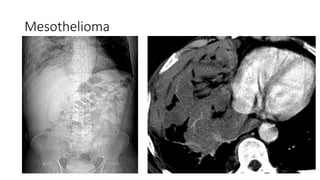

Mesothelioma

Asbestosis

• Workers in shipbuilding, roofing, and plumbing

industries asbestos used for insulation

• Calcified pleural plaques in the diaphragm and

posterolateral mid lung

• ↑ incidence of bronchogenic carcinoma and

1. bronchogenic carcinoma more common than

2. mesothelioma takes longer time to develop (25-

40 years) so is less common

3. smoking has no effect on mesothelium, but

amplifies the risk of bronchogenic carcinoma

when combined with asbestos

• No association with TB

• May also result in Caplan's syndrome